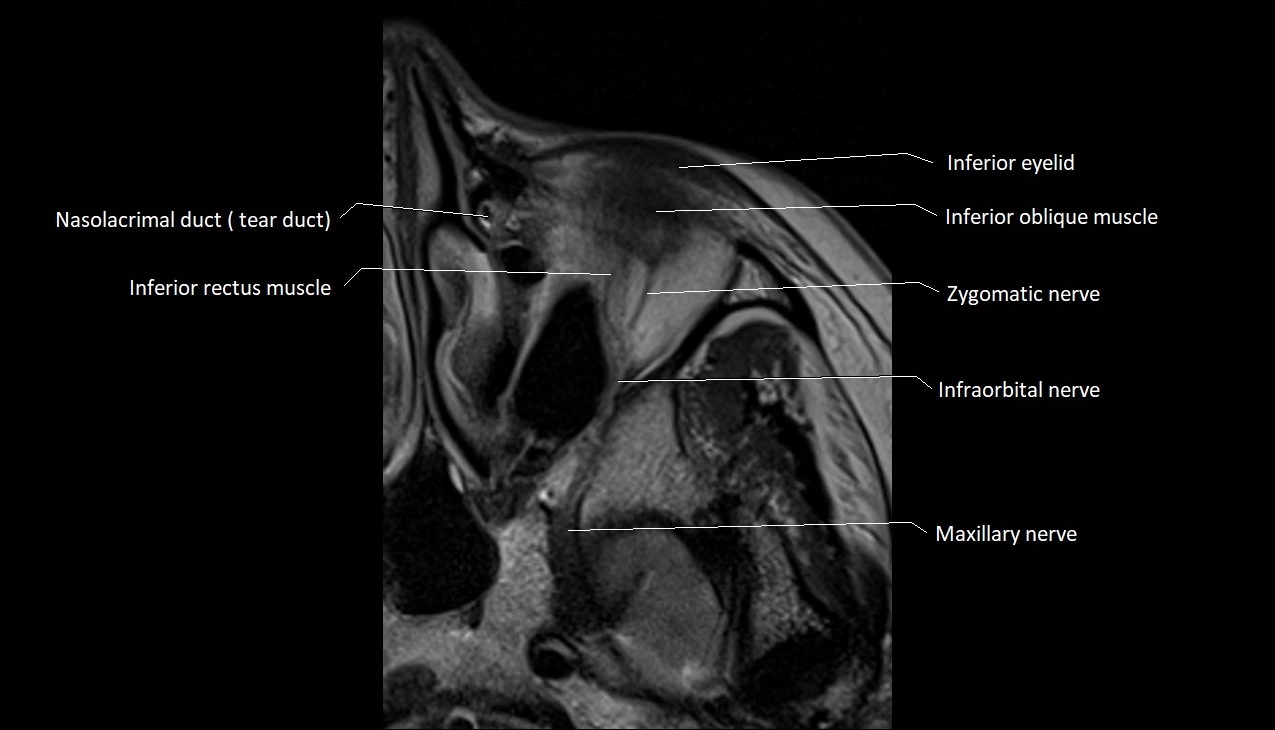

MRI images